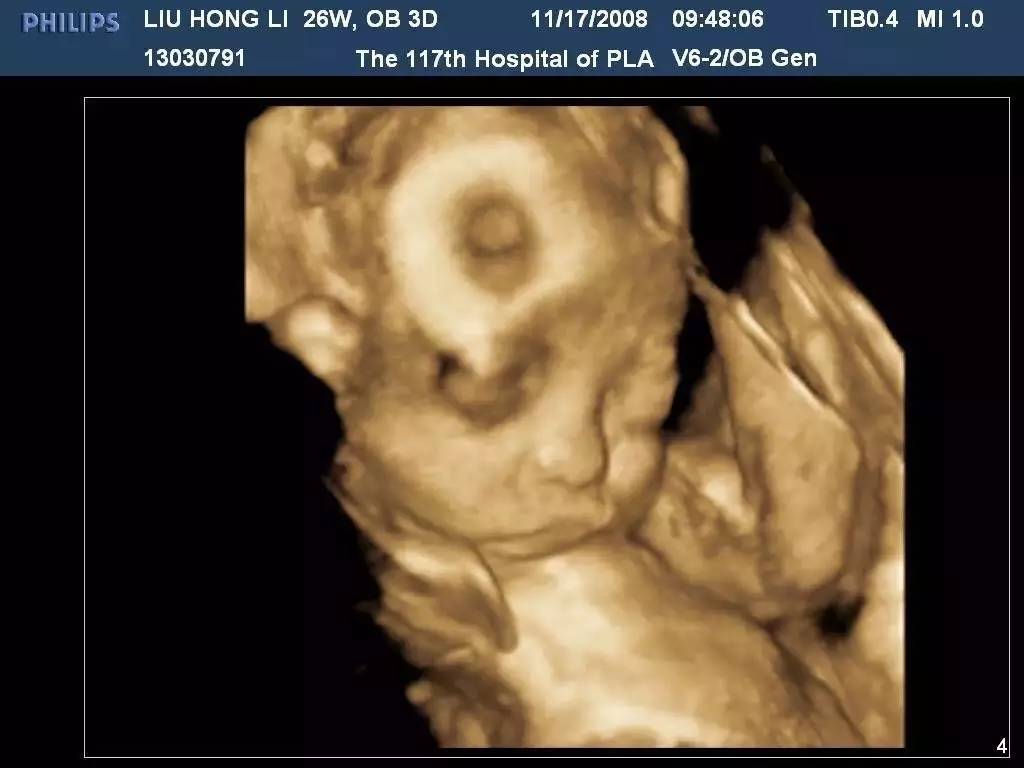

三維和四維彩超的區(qū)別在于一個(gè)“時(shí)間維”,三維彩超是靜態(tài)的,是某個(gè)時(shí)間點(diǎn)上的照片;而四維彩超是動(dòng)態(tài)的,由“零歲寫(xiě)真”升級(jí)成為“零歲錄像”。